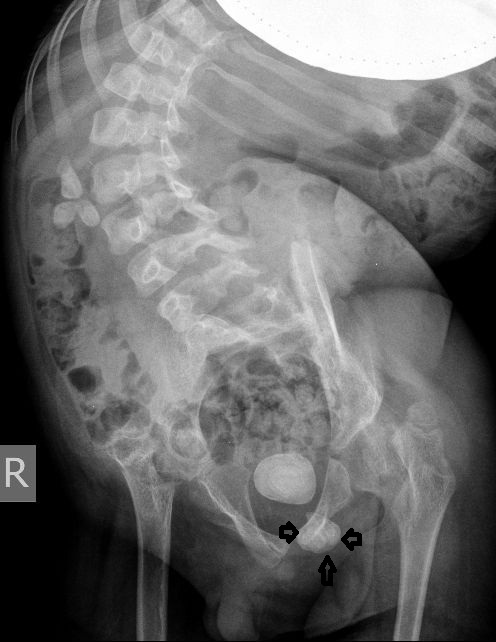

Для того, чтобы продемонстрировать степень ортопедических проблем и облегчить задание (или усложнить :) ) добавляю обзорную рентгенограмму брюшной полости

DX0001.jpg

Нейрогенный мочевой пузырь (?), МКБ, конкремент мочевого пузыря, двухсторонний мегауретер, конкремент правой почки.

И что законтрастировалось на экскреторных урограммах около мочевого пузыря?

DX0004.jpg

Если честно, и я изначально не совсем понял, где находится конкремент (а это конечно же конкремент), локализованный на урограммах. При первичном исследовании на УЗИ его я не видел (либо он спрятался за тенью конкремента мочевого пузыря, либо я обрадовался редкой находке конкремента такого размера в мочевом пузыре - 2.5 см, и не посмотрел что ниже). Тем не менее при ретроспективном анализе архивированных сонограмм, как мне кажется, он попал в один из сканов, м.б. не совсем чётко.

И всё -же, где конкремент :?:

Возможно, в дивертикуле либо в нижней трети мочеточника..